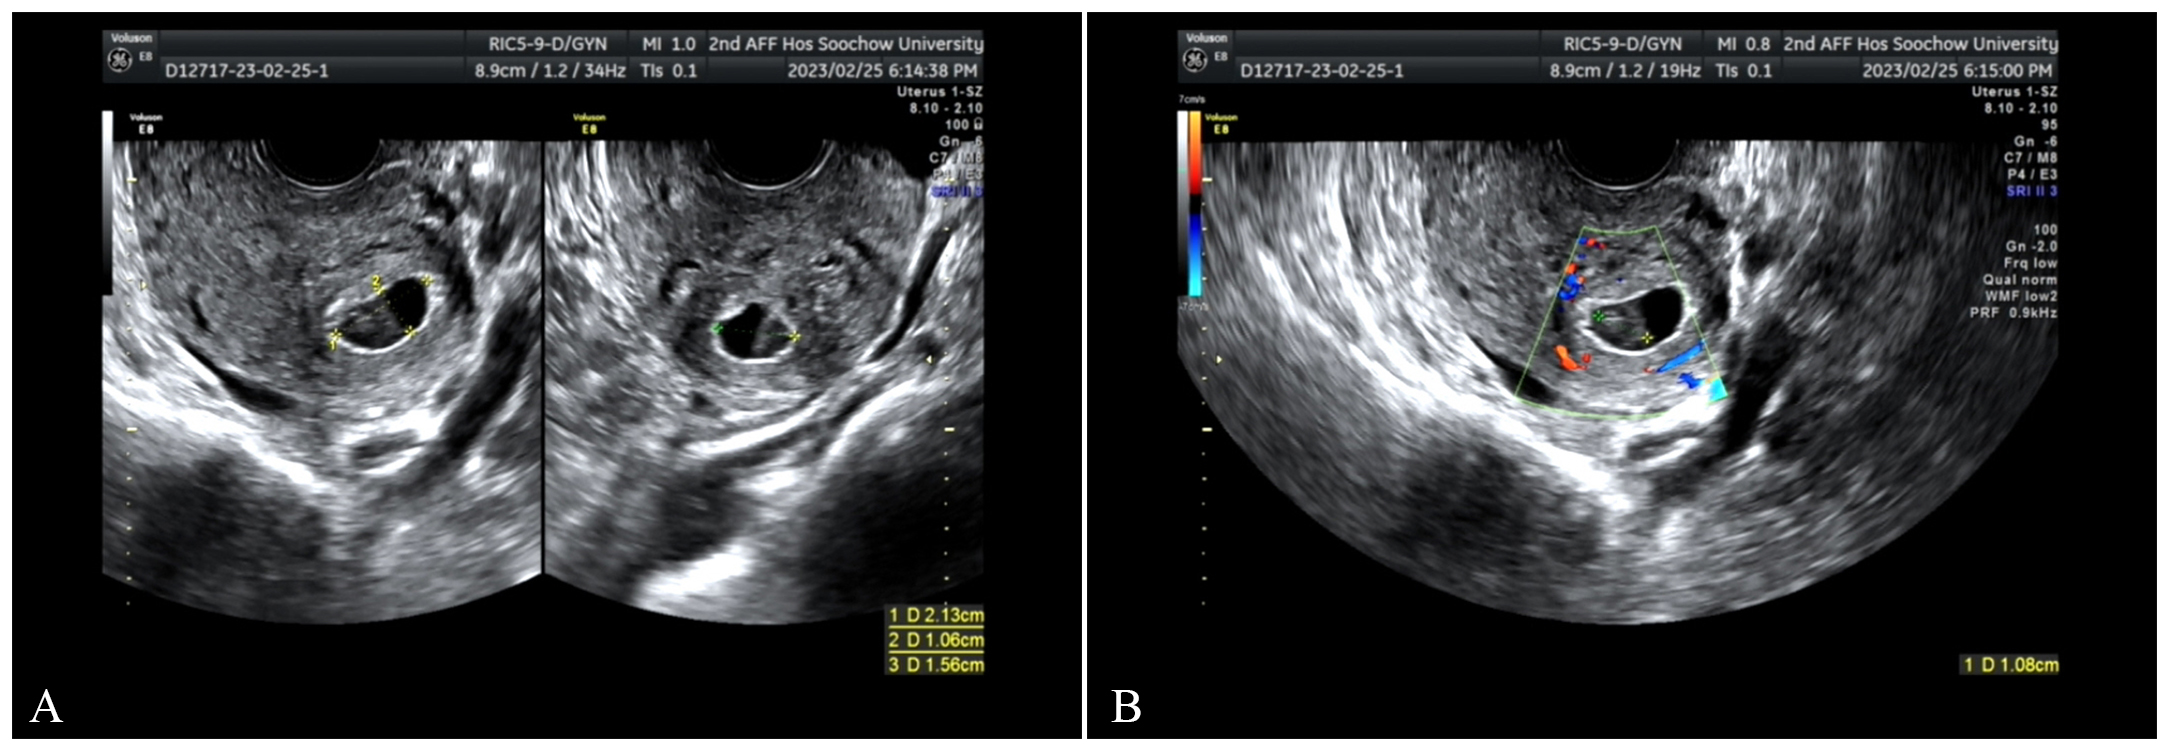

Fig. 1. On February 26, transvaginal ultrasound scan. (A) A gestational sac was seen near the uterine angle, measuring approximately 21 mm